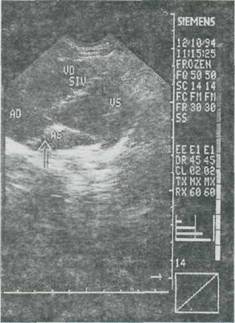

Echo īn modul M: demonstreaza "semne indirecte" de dilatatie ventriculara dreapta si miscare sistolica anormala a septului interventricular, semne constante daca volumul suntului este semnificativ. Echocardiografia bidimensionala permite localizarea exacta a comunicarii interatriale (incidenta subxifoidiana este cea mai recomandata). Se cere examenului sa precizeze raporturile cu vena cava superioara. Doppler pulsatil poate cuantifica suntul stānga-dreapta īn raport cu debitul sistemic si debitul pulmonar. Datorita preciziei acestor metode, metodele de diagnostic invaziv sunt tot mai rar indicate, si oricum, numai preoperator, pentru stabilirea exacta a dimensiunii defectelor ovalare.

Fig. 9-1. Defect septal atrial. Echocardiog rafie 2-D, transductor n pozitie apical 4 camere; sageata indica ntreruperea ecoului septai atriai in ostium secundam.